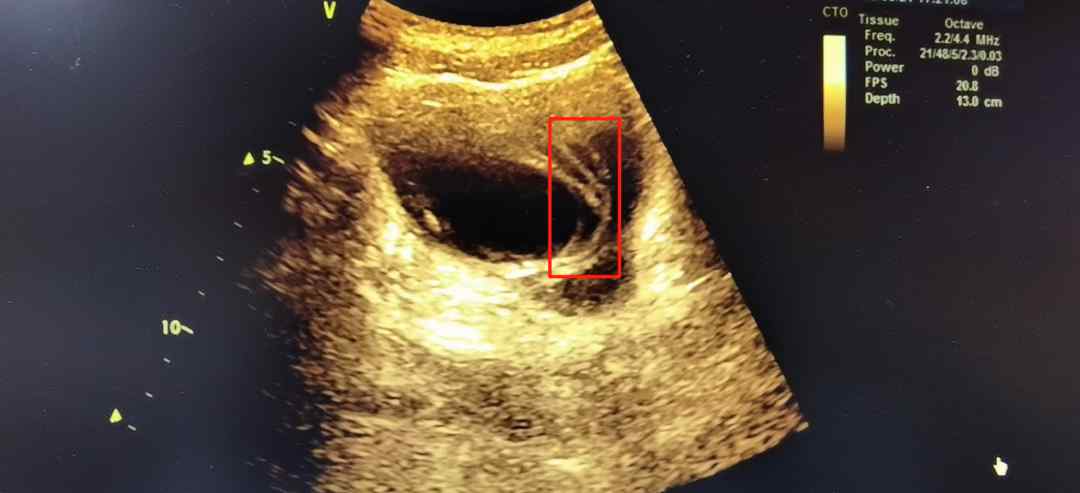

住院4天了,小明都不配合留取尿液进行尿常规检验。林医生对小明进行了耐心的解释,他才很不情愿的留取尿标本进行化验。结果提示小明存在泌尿系感染。经过进一步检查发现,小明膀胱里有异物。原来,一个月前小明曾将一条电线从尿道口塞进后未取出。

5月11日,小明被转入泌尿外科接受手术治疗。术中,医生从其膀胱中取出长约70cm的黄色金属丝胶皮电线。